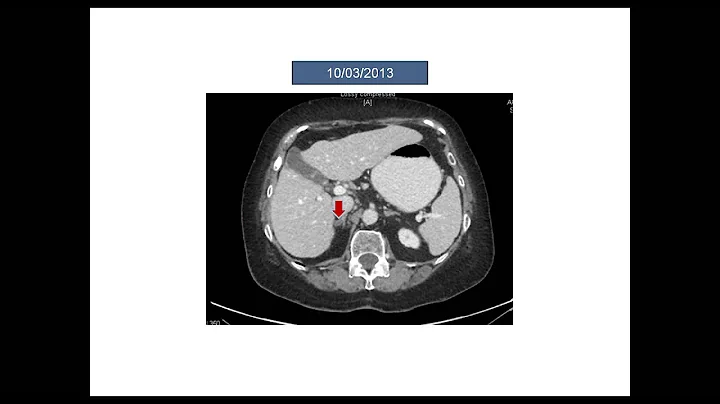

Case Study: Treating An Elderly Patient With Squamous Non-small Cell Lung Cancer

In the first installment of the series, moderator Corey J. Langer, MD, introduces the panelists and begins a case-based discussion ...